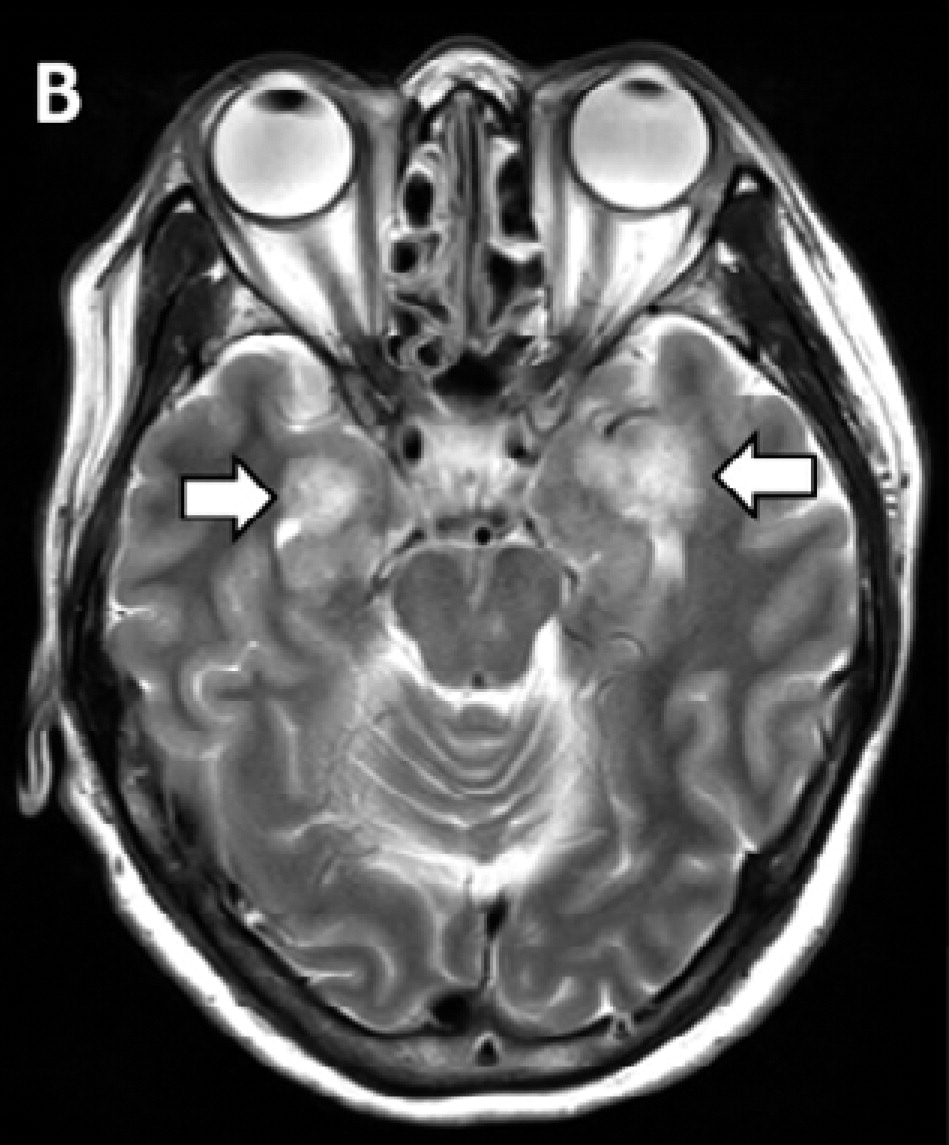

新型コロナウイルスの感染が全世界中で広がるなか、肺炎症状だけでなく、味覚や嗅覚などの異常も報告されるようになったが、米国の研究で、脳の一部で炎症や壊死が進行する「急性壊死性脳炎」を発症していたことが明らかになった。

米ミシガン州デトロイトのヘンリー・フォード・ヘルスシステムの神経科医エリッサ・フォーリー博士らの医療チームが放射線医学誌『ラジオロジー(Radiology)』に先月31日付で発表した症例報告によると、航空会社に勤務する58歳の女性は先月19日、パニック障害や方向感覚の欠如、意識不明などの状態で同病院に救急搬送された。

同時に、頭部のCTスキャン検査を実施したところ、脳の中心部分にあって、視覚や聴覚、運動などをつかさどる「視床」に損傷が見つかり、壊死が起きているのが判明。さらに脳のMRI検査の結果、側頭葉の血管が破裂して出血しているのも見つかった。

当初、急性脳炎を疑っていた医療チームは、免疫機能が暴走して、自身の体にダメージを与える「サイトカインストーム」を起こしていると判断。サイトカインとは、白血球など免疫系の細胞から分泌されるタンパク質で、ウイルスや病原体の増殖を抑えるなどといった役目を果たす。サイトカインストームとは

しかし、免疫系のバランスが乱れて、サイトカインの制御ができなくなると、サイトカインストームといってサイトカインの過剰分泌を起こし、ひどい場合は死に至ることもあるという。

ヘンリー・フォード・ヘルスシステムのチームは「新型コロナウイルスが原因で、急性壊死性出血性脳症を起こした初めての症例だ」として、現場で働く臨床医や放射線医は、この症状の進行に注意するよう呼びかけている。